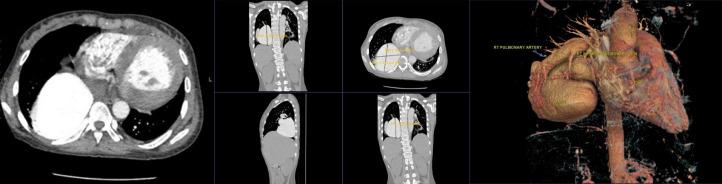

Chronic cyanosis since infancy: Unveiling a giant right pulmonary arteriovenous malformation.

Giant pulmonary arteriovenous malformations (PAVMs) are rare vascular anomalies involving direct connections between pulmonary arteries and veins, leading to right-to-left shunting and systemic hypoxemia. While small PAVMs may be asymptomatic, larger lesions often present with dyspnea, cyanosis, and related complications. An 18-year-old female with progressive dyspnea and cyanosis-first noted during infancy-was found to have a giant PAVM in the right lower lung lobe on thoracic computed tomography (CT). Imaging, particularly computed tomography (CT), was essential for diagnosis and treatment planning. This case underscores the need to consider PAVMs in the differential diagnosis of chronic cyanosis and highlights the critical role of radiologists in identifying and characterizing these lesions to guide appropriate management.and characterizing these lesions to support optimal clinical decision-making.